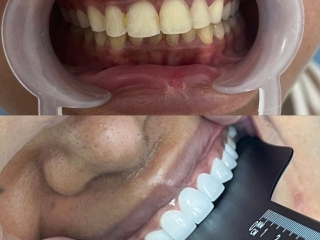

Cắt lợi làm dài thân răng và mài xương ổ cho KH Combodia – Giải pháp cho nụ cười cân đối, khỏe đẹp

Đó cũng là lý do mà khách hàng từ Cambodia đã không ngần ngại vượt hàng trăm km sang Việt Nam, tìm đến Nha Khoa Ân Đức Luxury để được bác sĩ Tài trực tiếp thăm khám và thực hiện cắt lợi làm dài thân răng kết hợp mài xương ổ.